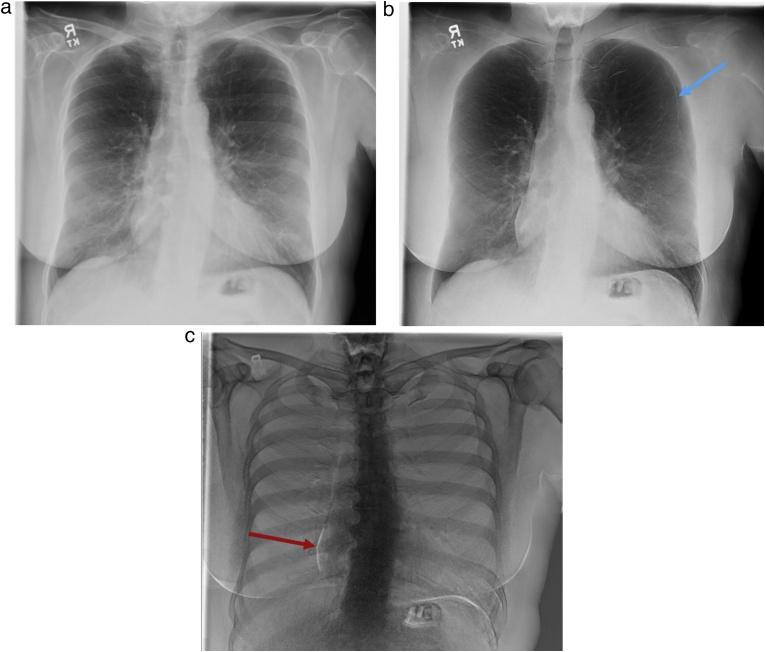

Recent advances in dual-energy imaging techniques, dual-energy subtraction radiography (DESR) and dual-energy CT (DECT), offer new and useful additional information to conventional imaging, thus improving assessment of cardiothoracic abnormalities. DESR facilitates detection and characterization of pulmonary nodules. Other advantages of DESR include better depiction of pleural, lung parenchymal, airway and chest wall abnormalities, detection of foreign bodies and indwelling devices, improved visualization of cardiac and coronary artery calcifications helping in risk stratification of coronary artery disease, and diagnosing conditions like constrictive pericarditis and valvular stenosis. Commercially available DECT approaches are classified into emission based (dual rotation/spin, dual source, rapid kilovoltage switching and split beam) and detector-based (dual layer) systems. DECT provide several specialized image reconstructions. Virtual non-contrast images (VNC) allow for radiation dose reduction by obviating need for true non contrast images, low energy virtual mono-energetic images (VMI) boost contrast enhancement and help in salvaging otherwise non-diagnostic vascular studies, high energy VMI reduce beam hardening artifacts from metallic hardware or dense contrast material, and iodine density images allow quantitative and qualitative assessment of enhancement/iodine distribution. The large amount of data generated by DECT can affect interpreting physician efficiency but also limit clinical adoption of the technology. Optimization of the existing workflow and streamlining the integration between post-processing software and picture archiving and communication system (PACS) is therefore warranted.

双能成像技术的最新进展,即双能减影X线摄影(DESR)和双能CT(DECT),为传统成像提供了新的有用的附加信息,从而改善了对心胸异常的评估。DESR有助于肺结节的检测和特征描述。DESR的其他优点包括能更好地显示胸膜、肺实质、气道和胸壁异常,检测异物和植入装置,改善心脏和冠状动脉钙化的可视化,有助于冠状动脉疾病的风险分层,以及诊断缩窄性心包炎和瓣膜狭窄等疾病。市售的DECT方法分为基于发射的(双旋转/自旋、双源、快速千伏切换和分束)和基于探测器的(双层)系统。DECT提供几种专门的图像重建。虚拟非增强图像(VNC)通过消除对真正非增强图像的需求来降低辐射剂量,低能量虚拟单能图像(VMI)增强对比度,有助于挽救原本无法诊断的血管研究,高能量VMI减少金属硬件或高密度对比剂引起的线束硬化伪影,碘密度图像允许对增强/碘分布进行定量和定性评估。DECT产生的大量数据可能会影响解读医生的效率,但也限制了该技术在临床上的应用。因此,有必要优化现有的工作流程,并简化后处理软件与图像存档和通信系统(PACS)之间的集成。